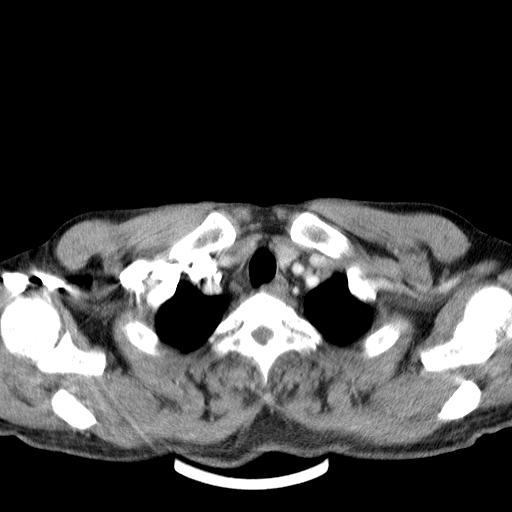

先行ct平扫,纵膈内多发软组织影,ct值约为36hu,以下为增强扫描和腹部平扫。

经典?纵膈多发肿大淋巴结。腹膜后未见异常。

淋巴瘤?胸腺瘤?

支持淋巴瘤

淋巴瘤可能